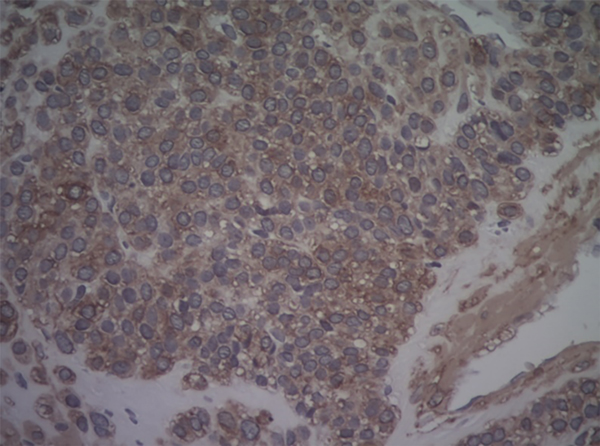

Se realizó tratamiento artroscópico de la rodilla a través de dos portales habituales AM y AL. Se constató plástica de LCA en pívot central y lesión meniscal interna, para la cual se realiza meniscectomía parcial. A continuación, se efectuó cirugía abierta, abordaje sobre masa tumoral y biopsia excisional de la pieza, de color parduzco que presenta bordes irregulares de 0.7 × 0.5 × 0.2 (figs. 3 y 4). El informe de anatomía patológica informa glomangioma como diagnóstico de la pieza enviada (figs. 5 y 6).

Figura 6: Glomangioma. 40X. AML.